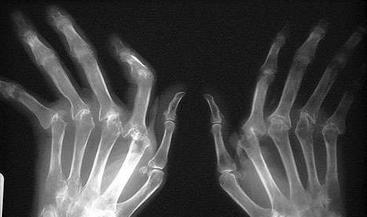

生物3D科技公司Organovo最近宣布與(yu) 加利福尼亞(ya) 大學達成合作。UCSF正在努力開發先進的生物3D打印組織,這一研究將用於(yu) 骨骼疾病的治療。